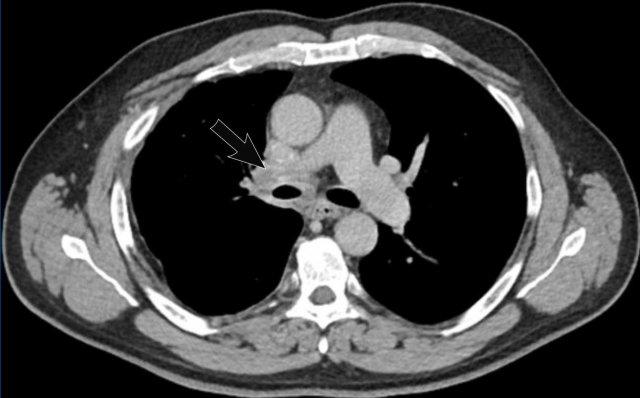

Hình ảnh

Viêm trung thất xơ hóa bên phải ở nam giới 51 tuổi, cho thấy tổn thương tỷ trọng mô mềm xung quanh phế quản chính phải (mũi tên).

Cùng bệnh nhân.

Có các dấu hiệu thứ phát của chèn ép đường thở trung tâm và mạch máu, với mất thể tích phổi khu trú và dày mô kẽ do phù nề.